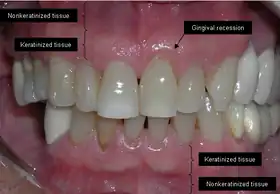

Gums showing recession

The soft tissue in the oral cavity is classified as either keratinized or nonkeratinized based on the presence of keratin in the epithelium.[4] In health, the soft tissue immediately around the teeth is keratinized and is referred to as keratinized tissue or gingiva. Alveolar mucosa is non keratinized oral epithelium and is located apical to the keratinized tissue, delineated by the mucogingival junction (MGJ). It should also be pointed out that mucosa can surround a tooth in health.[5] Nonkeratinized tissue also lines the cheeks (buccal mucosa), underside of the tongue and floor of the mouth. The lips contain both non-keratinized tissue (on the inside) and keratinized tissue on the outside, demarcated by the vermillion border. The dorsum of the tongue is keratinized and features many papillae, some of which contain taste buds.[6]

Exposure of the tooth root due to loss of keratinized tissue around the neck of a tooth is referred to as gingival recession. This can result in sensitivity or pain from the exposed tooth root surface (dentin is more permeable and soft compared to enamel and dentin is what makes up the tooth root).[7] Recession may also cause an unasthetic appearance especially if located in the anterior dentition (front teeth). While not all cases of gingival recession require surgical correction, there are various options if that is what the patient desires.[8] It should be reinforced that recession left untreated will not result in tooth loss, contrary to popular belief. Also, recession that is left untreated can be maintained and the inflammation kept at bay with proper brushing and oral hygiene technique.[5] On the other hand, if one desires to pursue corrective therapy, there are a wide variety of techniques ranging from autograft (your own tissue, usually taken from the palate), allograft (someone else's tissue, cadaver), xenograft (animal, usually porcine or bovine) or simply repositioning of the tissue native to the site.[9] The benefits of corrective therapy often result in decreased sensitivity through coverage of the root surface in addition to a gain in the keratinized tissue mentioned beforehand.